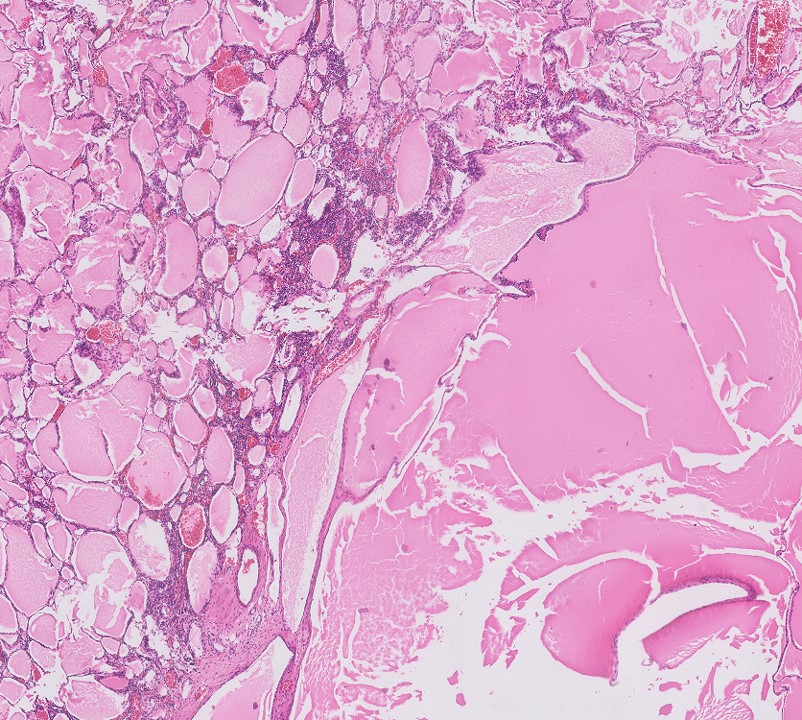

Microscopic (histologic) description

- Cysts lined with flat / cuboidal / hobnail cells (or are denuded)

- Epithelial elements consist mainly of mature and immature / abortive tubules and small papillae resembling immature glomeruli

- Key histological findings of the variably cellular septa include

- Nephroblastomatous epithelial elements

- Islands of undifferentiated blastema and differentiated mesenchymal elements (skeletal muscle and less often cartilage and fat) (J Urol 2010;183:1585)

- Focally, the septal elements may protrude into the cystic spaces in microscopic papillary folds

Microscopic (histologic) images

Contributed by Americo Brilhante, M.D. and Daniel Athanazio, M.D., Ph.D.